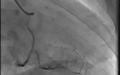

coronary angiogram